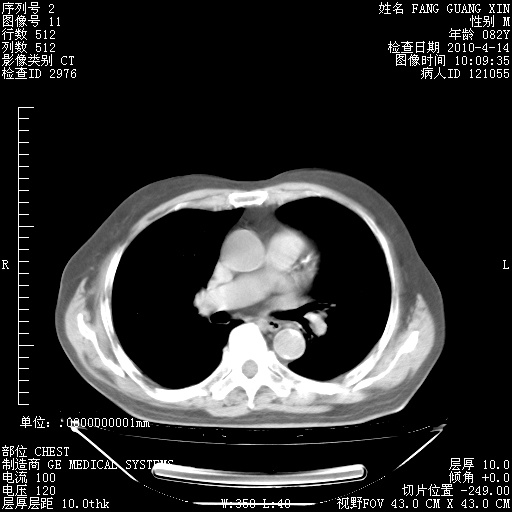

肺部CT平扫未见异常。